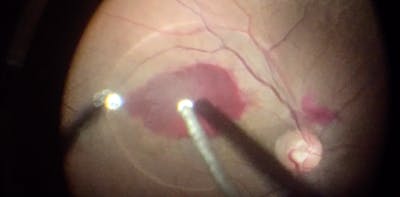

The RETINAWS panel led by Kourous Rezaei, MD, discuss techniques for vitreoretinal surgery and rare surgical cases.